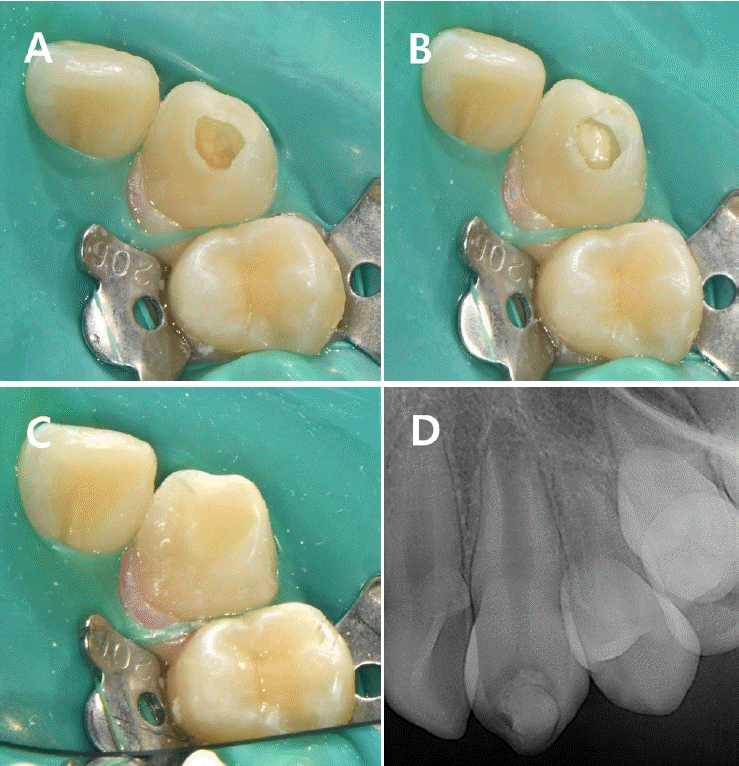

10세 여아가 미맹출된 하악 좌측 제2대구치의 방사선 투과상이 관찰된다는 주소로 개인 의원에서 조선대학교 치과병원 소아치과에 의뢰되었다. 환아는 특이 의학적 병력이 없었고, 임상적으로도 증상은 나타나지 않았다. 내원 당시 구강 내 임상 검사에서는 특이 소견이 관찰되지 않았으며, 방사선학적 검사에서 미맹출된 하악 좌측 제2대구치의 치관부에 방사선 투과상이 확인되어 PEIR으로 진단하였다(Figs. 1A and B).초진 당시 병소의 위치가 깊어 치은판절제술을 시행하더라도 접근이 어려울 것으로 판단되었으며, 이에 따라 6개월 간격의 정기검진을 통해 병소의 진행 양상과 맹출 상태를 관찰하며 적절한 치료 시기를 결정하기로 하였다.6개월 후 내원하여 촬영한 파노라마방사선사진에서 해당 치아의 맹출이 진행 중인 것이 확인되었고, 병소의 크기나 형태에는 변화가 없어 추가 맹출 이후 수복하기로 계획하고 6개월 뒤 재내원을 안내하였다(Fig. 1C). 초진으로부터 12개월 경과 시 하악 좌측 제2대구치는 여전히 출은하지 않았으나, 하악 우측 제2대구치의 출은이 확인되어 내원 간격을 3개월로 조정하였다(Fig. 1D).3개월 후 재내원 시 하악 좌측 제2대구치의 출은이 관찰되어 수복 치료를 시행하기로 결정하였다(Fig. 2A). 국소마취하에 치은판 절제술을 시행하여 치관 전반을 노출하였고 협면과 교합면에 걸쳐 흡수성 와동이 확인되었다. 특히 협측에 깊은 병소가 존재하였으며, 와동 내부는 연조직으로 채워져 있었다. 병소를 저속 핸드피스와 수기구를 이용하여 제거한 후, 광중합형 GI (Riva Light Cure, SDI, Victoria, Australia)로 충전하였다.- 증례 2

Figure 1.

Preoperative radiographs. A radiolucent lesion is observed in the coronal portion of tooth #37. A. Panoramic view at the initial visit. B. Periapical view at the initial visit. C. Panoramic radiographs taken during the follow-up period. At 6 months, an eruptive pattern of tooth #37 is observed. D. At 12 months, tooth #47 begins to emerge through the gingiva.

Figure 2.

Radiographs and intraoral photographs during treatment. A. Periapical radiograph taken at 15 months. A decision is made to proceed with restorative treatment. B. Periapical radiograph taken at six-month follow-up after restoration. C. Intraoral clinical photograph after restoration.